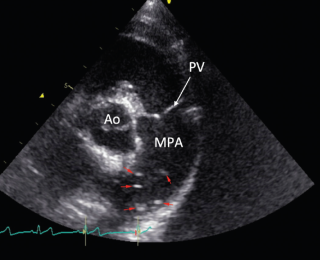

Thoracic radiographs revealed enlargement of the pulmonary arteries, mild to moderate right ventricular enlargement and a moderate diffuse, unstructured interstitial pattern with patchy alveolar areas within the right cranial and middle lung lobes (see Figures 1 and 2). Echocardiography revealed right atrial enlargement with bulging of the interatrial septum to the left, mild subjective enlargement of the right ventricle and mild to moderate central pulmonic regurgitation with a mildly elevated velocity (2.8m/s; reference value <2.2m/s). The pulmonary artery was mildly enlarged and contained multiple mobile, tortuous linear hyperechoic structures, likely to reflect the presence of adult worms (see Figure 3). The laboratory test results in combination with the imaging findings were consistent with a diagnosis of canine dirofilariasis.